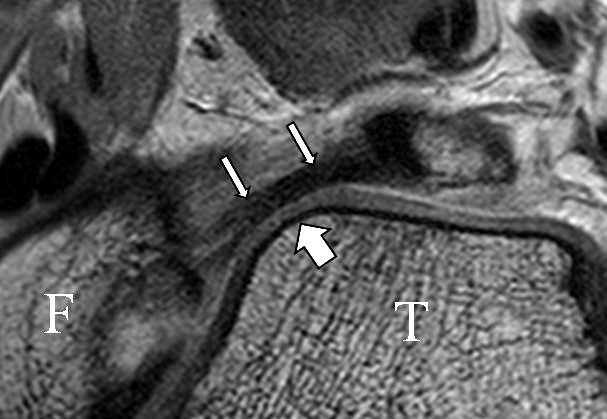

Jedoch findet man sich auch hier mit dem Problem der in den Standard-Projektionen schräg verlaufenden Syndesmose konfrontiert. Der oligofaszikuläre Aspekt der vorderen Syndesmose kann in der axialen Schnittebene eine zum Verwechseln ähnliche Morphologie wie eine Ruptur aufweisen (Abb. 15 b und c). Doppelangulierte Schnitte entlang der Achse (schräg koronar/schräg sagittal) lassen hingegen eine eindeutige Beurteilung der Bandstrukturen zu (Abb. 16) und verbessern die Syndesmosendiagnostik.

Bezogen auf die Transversalebene verläuft die Syndesmose ca. 30° schräg cranio-caudal anguliert (Abb. 15 a). Häufig lassen sich drei Hauptfaszikel differenzieren: das kürzeste superiore, das stärkste mittlere und das längste kaudale Faserbündel. Ein akzessorisches Bündel, das anteriore-inferiore, tibiofibulare Ligament (AITFL) oder auch Bassett-Ligament wird in 80-94% der Patienten nachgewiesen 8. Dies weist einen unmittelbaren Bezug zur anterolateralen Talusschulter auf (Abb. 17). In Kombination mit einer Außenbandinstabilität und konsekutivem, talarem Vorschub kann dieses zu einem Impingement an der anterolateralen Taluskante führen mit nachfolgender chondraler oder osteochondraler Läsion.

b. T2 fs axial. Infraktion des hinteren Volkmann‘schen Dreiecks (schmale, weiße Pfeile). Hier inserierende, intakte, hintere Syndesmose (breite, weiße Pfeile).

Da also die hintere Syndesmose an der posterioren Tibia inseriert, entspricht eine Fraktur oder Infraktion des hinteren Volkmann`schen Dreiecks funktionell einem knöchernen Ausriss des Ligamentum tibiofibulare posterius (Abb. 18 a und b). Aufgrund der Koinzidenz von Syndesmosenläsionen mit Innenbandverletzungen ist bei der Beurteilung gesondert auf solche zu achten.